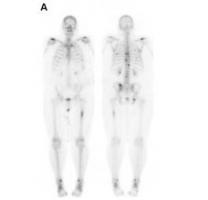

Actualité publiée il y a 4 années 1 moisCANCER de la PROSTATE: Le nouvel agent d'imagerie qui identifie plus tôt et plus précis